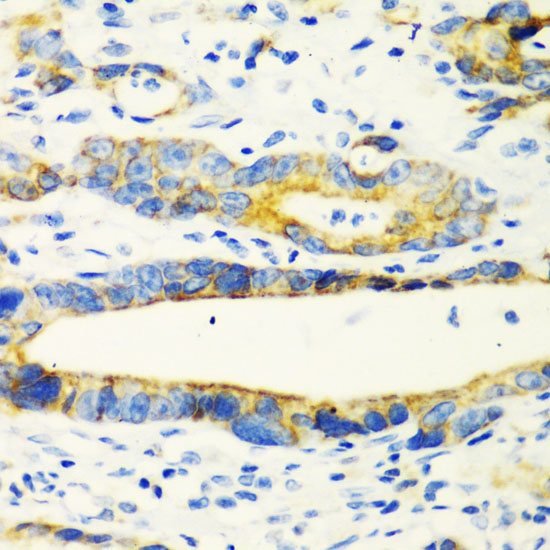

Contributes to the response to IL-13 and inflammation in response to IL-13. Stimulates chemokine production by pulmonary epithelial cells.

Detected in lung epithelial cells from asthma patients (at protein level). Highly expressed in stomach. Detected at lower levels in lung.

[Isoform 1]: Secreted. Secretion depends on EGFR activity.; [Isoform 2]: Cytoplasm.; [Isoform 3]: Cytoplasm.